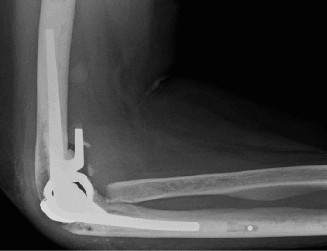

She has received multiple corticosteroid injections into her elbows over the past 3 years, but she no longer gets relief. Her images are shown (Figs. 2–99 to 2–102).

Figure 2–99

Figure 2–100

Figure 2–101

Figure 2–102

Approximately what percentage of patients with rheumatoid arthritis develop elbow involvement within 5 years?

The correct answer is (E). Between 20% and 50% of patients with rheumatoid arthritis will develop elbow arthritis. Isolated presentation of the elbow is rare and only occurs about 5% of the time. Care should be given to provide the best treatment for the entire upper extremity when evaluating and treating a patient with rheumatoid arthritis.

Which of the following is the procedure of choice when treating an advanced, debilitating rheumatoid elbow?

- Semi-constrained total elbow

Discussion

The correct answer is (E). Semi-constrained total elbow is the definitive procedure of choice when treating an elbow with extensive articular damage and subluxation or ankylosis of the joint (see Fig. 2–103). Rheumatoid patients place a lower demand on the prosthesis than patients with primary osteoarthritis (OA), and thus have a lower incidence of mechanical loosening. Due to the ligamentous laxity, prosthetic instability is the complication that most commonly inhibits success.